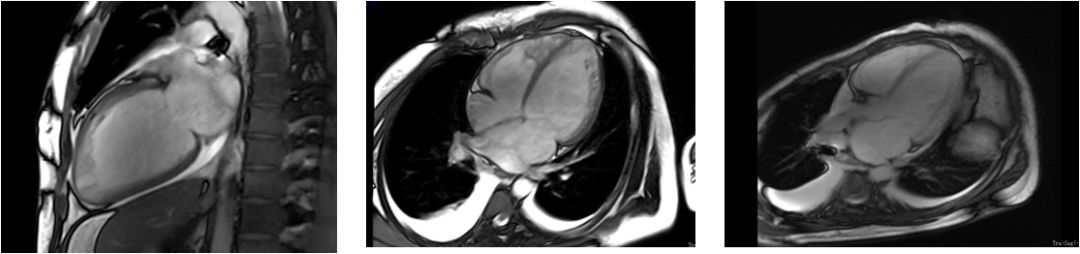

✦ 若根据超声心动图表现不能确定诊断,可使用CMR

✦ CMR可为左室所有节段提供良好的空间分辨率,包括心尖部和侧壁。

▶▷ 2018年10月29日-31岁男性,心力衰竭入院